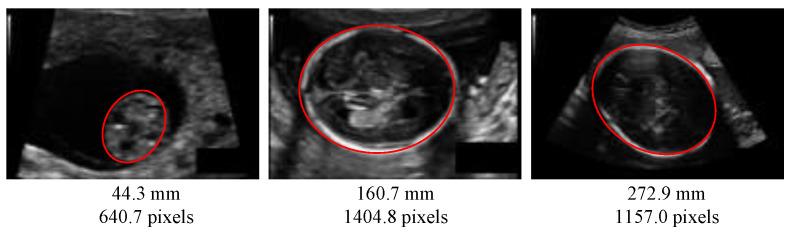

基于分割与基于回归的生物标志物估计:以超声图像评估胎儿头围为例

Segmentation-Based vs. Regression-Based Biomarker Estimation: A Case Study of Fetus Head Circumference Assessment from Ultrasound Images.

The fetus head circumference (HC) is a key biometric to monitor fetus growth during pregnancy, which is estimated from ultrasound (US) images. The standard approach to automatically measure the HC is to use a segmentation network to segment the skull, and then estimate the head contour length from the segmentation map via ellipse fitting, usually after post-processing. In this application, segmentation is just an intermediate step to the estimation of a parameter of interest. Another possibility is to estimate directly the HC with a regression network. Even if this type of segmentation-free approaches have been boosted with deep learning, it is not yet clear how well direct approach can compare to segmentation approaches, which are expected to be still more accurate. This observation motivates the present study, where we propose a fair, quantitative comparison of segmentation-based and segmentation-free (i.e., regression) approaches to estimate how far regression-based approaches stand from segmentation approaches. We experiment various convolutional neural networks (CNN) architectures and backbones for both segmentation and regression models and provide estimation results on the HC18 dataset, as well agreement analysis, to support our findings. We also investigate memory usage and computational efficiency to compare both types of approaches. The experimental results demonstrate that even if segmentation-based approaches deliver the most accurate results, regression CNN approaches are actually learning to find prominent features, leading to promising yet improvable HC estimation results.

胎儿头围(HC)是监测孕期胎儿生长的关键生物特征,可通过超声(US)图像进行估算。自动测量HC的标准方法是使用分割网络对头骨进行分割,然后通常在进行后处理后,通过椭圆拟合从分割图中估计头部轮廓长度。在这个应用中,分割只是估计感兴趣参数的一个中间步骤。另一种可能性是使用回归网络直接估计HC。即使这种无分割方法通过深度学习得到了改进,但直接方法与分割方法相比的效果如何尚不清楚,分割方法预计仍然更准确。这一观察结果激发了本研究,我们提出对基于分割和无分割(即回归)的方法进行公平、定量的比较,以估计基于回归的方法与分割方法的差距。我们对分割和回归模型的各种卷积神经网络(CNN)架构和主干进行了实验,并在HC18数据集上提供了估计结果以及一致性分析,以支持我们的发现。我们还研究了内存使用情况和计算效率,以比较这两种方法。实验结果表明,即使基于分割的方法能提供最准确的结果,但回归CNN方法实际上正在学习找到突出特征,从而得出有前景但仍有待改进的HC估计结果。